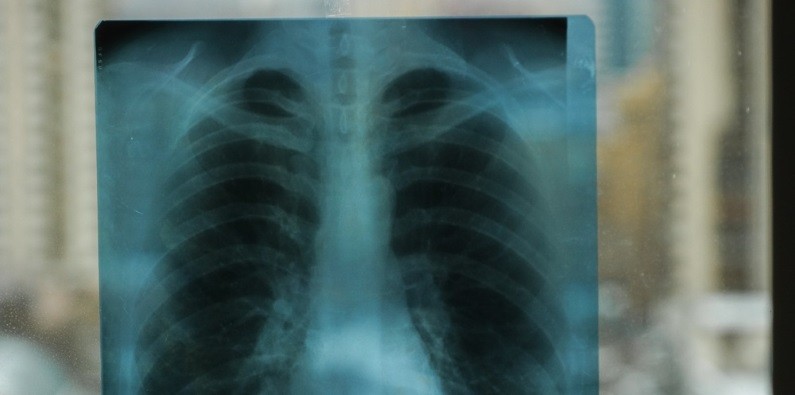

Как отметила Елена Чернышева, лечение заболевания сложное и во многом зависит от стадии. Так, на начальной стадии таблетки могут приостановить процесс заражения. Чаще всего оно выявляется уже тогда, когда нужно хирургическое удаление образовавшихся пузырей, то есть части ткани или органа. В противном случае пузырь может лопнуть и привести к аллергическому шоку или даже летальному исходу.

По последним данным, заболевание эхинококкозом обнаружено у 25 курсантов, у одного учащегося диагноз не подтвердился. Осложнений, а также поражений и изменений в головном мозге заболевших не обнаружено. Замминистра здравоохранения Ульяновской области Инна Чигирева назвала маловероятным пищевой путь заражения, поскольку личинки паразита погибают при температуре 60 градусов.